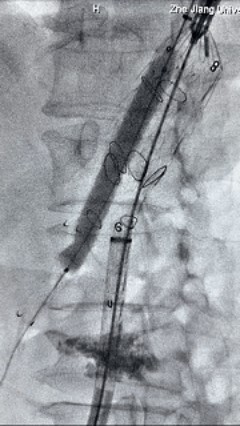

3. 经右股动脉导入超硬导丝,然后导入先健G-Branch 胸腹主动脉主体覆膜支架TAAA3418120e7i1010 一枚,释放主体支架至内分支打开,然后经左侧肱动脉入路,抓捕预置导丝成功后,将长鞘进入内分支出口处。

4. 经长鞘导入导管后,超选入腹腔干动脉,送入先健覆膜支架10*80mm一枚,近端重叠内分支,远端重叠腹腔干动脉,并予以10mm球囊后扩,手推造影显影良好。

5. 撤出腹腔干导丝导管,经左肱动脉长鞘继续抓捕预置导丝将长鞘超选至另一侧内分支,后超选进肠系膜上动脉,沿导丝送入先健覆膜支架10*100mm一枚,近端重叠内分支,远端重叠于肠系膜上动脉,并予以10mm球囊后扩,手推造影显影良好。

6. 解除束径,打开近端后释放,经肱动脉长鞘超选支架外分支,并进一步超选右侧肾动脉,交换加硬导丝,送入覆膜支架6*50mm和7*60mm各一枚,并予以球囊后扩张,手推造影显影良好。

7. 经长鞘重新选入左侧外分支,并超选进左肾动脉,沿导丝送入外周血管覆膜支架7*60mm一枚,并予以球囊后扩张,手推造影显影良好。